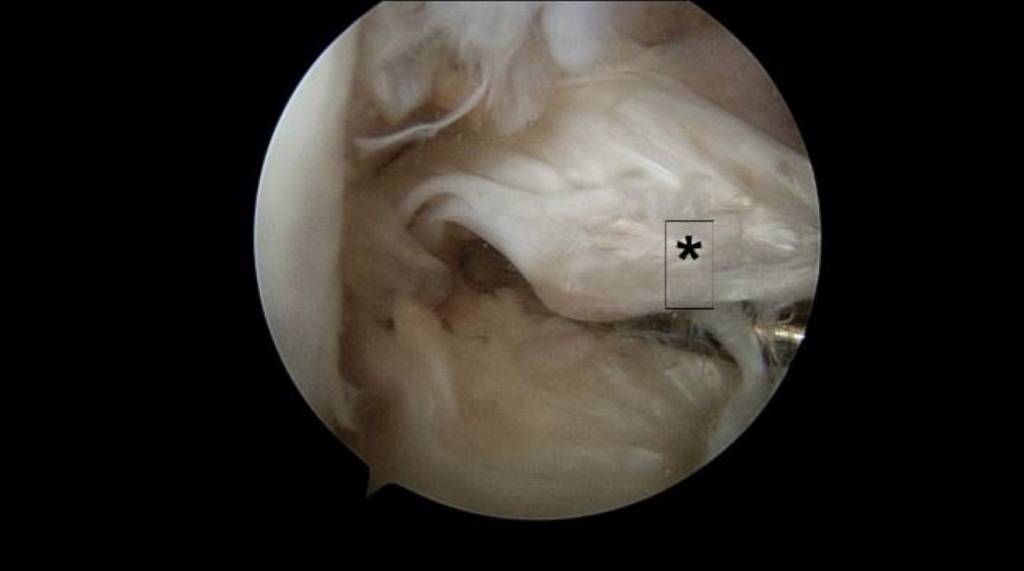

肩袖肌腱拉傷或撕裂的症狀視乎受傷程度而定。急性撕裂創傷的患者可能會感受到肩膀出現「啪」一下的響聲,隨即出現疼痛,腫脹以及無力的症狀。但部分拉傷的個案初期未必有十分明顯的疼痛或不適,可能於受傷過後的一至兩天才會逐漸出現。嚴重的肩袖肌腱撕裂(見圖二),會導致疼痛及乏力,影響生活或運動能力,醫生多會建議利用微創關節鏡手術進行修補。